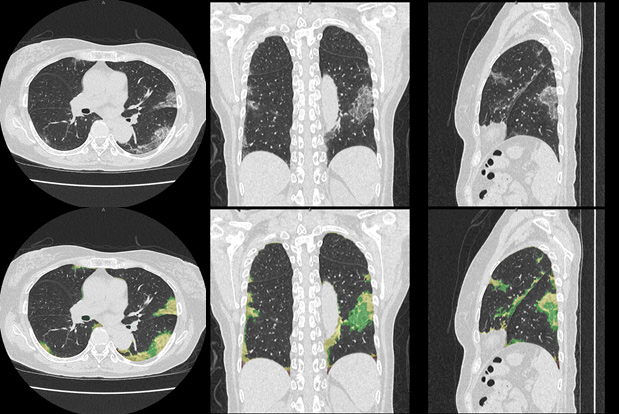

今回の適用評価で用いるびまん性肺疾患を中心としたCTテクスチャー解析は、本学とキヤノンメディカルが共同研究で開発した技術です。本解析技術は、CT画像を用い、様々な肺疾患の結果生じる肺の陰影・形状情報から、正常肺、すりガラス影、網状影、浸潤影、蜂巣肺、粒状影や気腫性病変など、肺の7種類の形態的特徴を、機械学習によって識別し定量化するものであり、基礎的な研究成果はすでに各種学会で報告され、間質性肺炎の重症度と解析による定量的な結果に相関があること1) 2)、放射線科医と解析による所見の一致度が十分であること3) 4)が示されています。2020年7月末から本解析技術を用いて新型コロナウイルス肺炎疑いの症例を解析し、臨床への適用評価を進めていきます。

新型コロナウイルス肺炎のCT診断画像及びその解析結果(上段 原画、下段 解析結果)